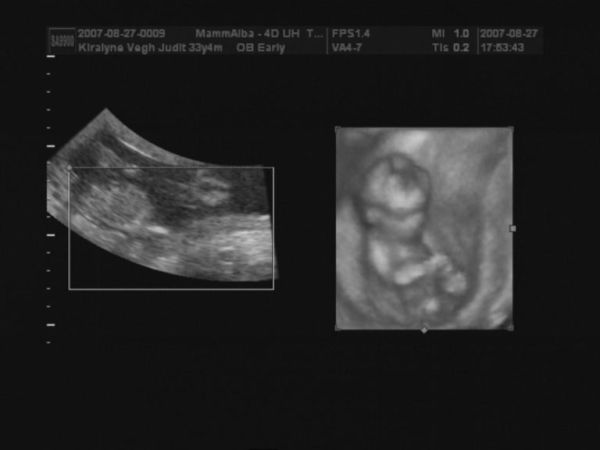

Judy, nagyon szép babátok van, gyerekek mit szóltak???